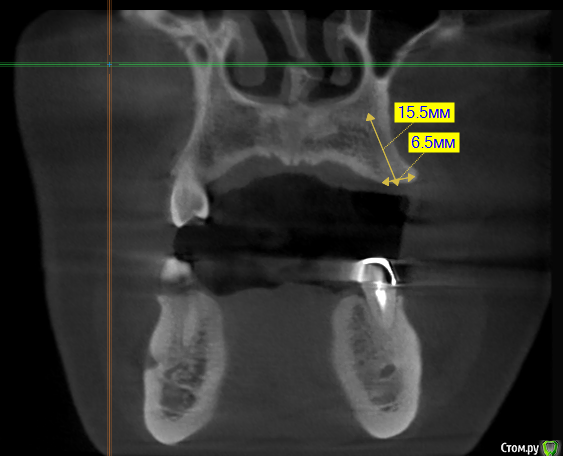

kramer Опубликовано 16 мая, 2018 Поделиться Опубликовано 16 мая, 2018 Коллеги, здравствуйте. Подскажите, пожалуйста, какое положение имплантата будет наиболее оптимальным? Область 24. Ставить под углом и в последствии угловой абатмент или прямо, но с риском для кортикалки? или нечто третье? Ссылка на комментарий

kramer Опубликовано 16 мая, 2018 Автор Поделиться Опубликовано 16 мая, 2018 Срез не верный. Переделал. Как-то так. Ангуляция имеется Ссылка на комментарий